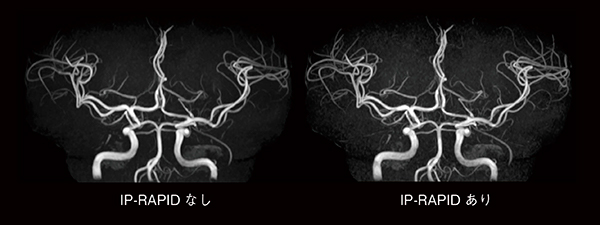

図3および図4は,従来のルーチンプロトコールと,IP-RAPIDを適用して撮像時間を短縮したプロトコールで撮像した,頭部T2横断像と頭部MRAのMIP画像の比較です。IP-RAPIDにより,同程度の画質ながら撮像時間がほぼ半分になっていることがわかります。撮像時間の短縮は検査時間全体の短縮に寄与し,被検者の心身的負担軽減が期待できます。一方,同じ撮像時間ならば,より分解能の高い画像を得ることが可能になると考えられます(図5)。ルーチン画像を短時間で取得することで検査時間枠に余裕が生まれ,異なる断面やシーケンスによる追加撮像が可能になると思われます。このように撮像時間の短縮は検査時間の短縮のみならず,検査内容の充実に対しても貢献し,被検者への手厚い医療が提供できると考えられます。

図4 MRA(MIP画像)におけるIP-RAPID有無の比較

撮像時間が半分以下においても,同等の画質が得られている。